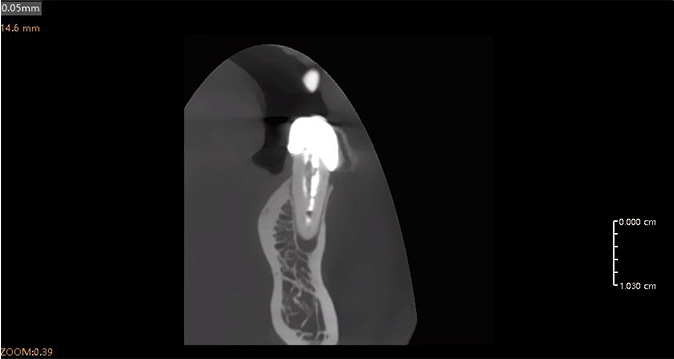

Análisis Endodóntico Impulsado por IA

El módulo de endodoncia de IA detecta y aísla automáticamente cada diente, proporcionando tres modos de visualización 3D: superficie, conducto radicular y transparencia. Esto permite una observación precisa de la morfología, el número y el detalle del conducto radicular, ayudando a los clínicos a realizar diagnósticos y mediciones precisas con facilidad.

Al-Powered: detección rápida y precisa de enfermedades

Precisión impulsada por IA: visualización óptima de las condiciones

Herramientas mejoradas para la comunicación con los pacientes